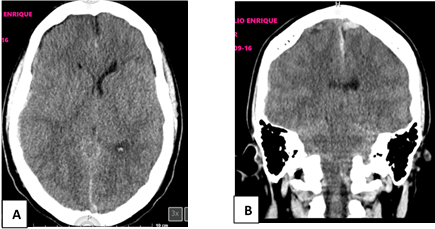

33-year-old male, with no history of chronic-degenerative diseases. His condition began on April 20, 2022 with tinnitus in the left ear, paresthesias were added in the 4 extremities, he attended a medical evaluation on 2 occasions, received unspecified treatment, later chest pain, anxiety, exacerbation of cognitive distortion and hypertensive lack of control, frontoparietal headache 7/10, epiphora and left conjunctival hyperemia. On May 2, presented an episode of psychosis, aggression and a new convulsive event, subsequently maniest inattention, altered judgment, 4 convulsive events lasting approximately 2-3 minutes, accompanied by hallucinations, incoherent and disorganized language. A lumbar puncture was performed reporting clear cerebrospinal fluid with increased protein, normal glucose and no cellularity. On May 5, a CT scan (Computerized Axial Tomography) of the simple skull was performed, which reported Fisher grade III subarachnoid hemorrhage, diffuse edema with displacement of the midline on the left side of up to 2.8 mm (Figure 1).

Figure 1 Cross-sectional and coronal cross-sectional computed tomography of the skull.

Simple cross-sectional tomography of the skull Figure-A, coronal section Figure-B, reports Fisher grade III subarachnoid hemorrhage, diffuse edema with displacement of the midline on the left side of up to 2.8 mm. Magnetic resonance imaging was performed on T2 and Flair sequences, which reported diffuse supratentorial cerebral edema, as well as the presence of Fisher grade III subarachnoid hemorrhage, predominantly on the right (Figure 2).